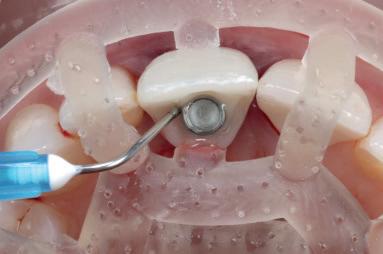

Case 1: Anterior tooth restoration with composite

Case 2: Posterior tooth restoration with composite

Restorations with BEAUTIFIL II LS, BEAUTIFIL Flow Plus X and OneGloss by Erik-Jan Muts, M.Sc., Netherlands